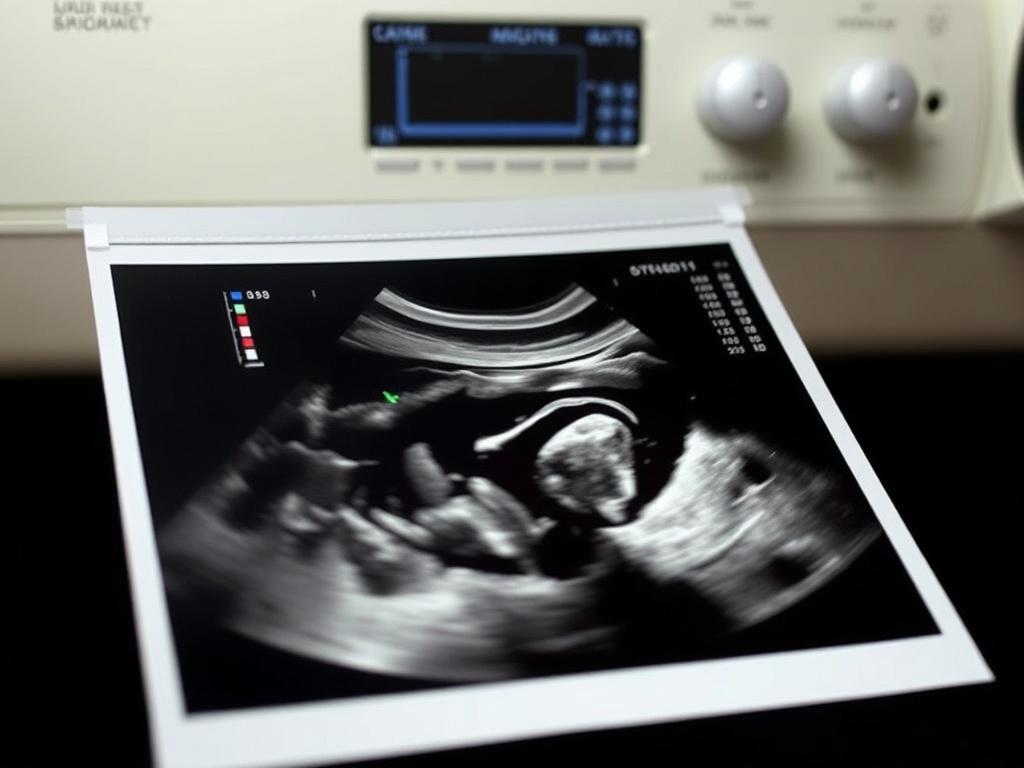

УЗИ органов малого таза — это понятное исследование, которое помогает быстро понять, как работают матка и яичники у женщин, простата и семенные пузырьки у мужчин, а также мочевой пузырь у всех. Врачу важно видеть картинку «здесь и сейчас», без боли и разрезов. В СМ-Клиника https://www.sm-eko.ru/diagnostika-besplodiya/zhenskogo/uzi-organov-malogo-taza/ это исследование занимает немного времени, дает четкий план действий и снимает лишние тревоги.

Вы приходите, раздеваетесь до пояса, ложитесь на кушетку. Врач наносит гель, прикладывает датчик и просит повернуться на бок или задержать дыхание. Процедура длится 10–20 минут. Боли нет. Неприятные ощущения возможны при вагинальном или ректальном доступе, но они краткие и умеренные. Сразу после УЗИ вы получаете описание и снимки. Врач объясняет, что видно, на простых примерах и без сложных слов.

УЗИ малого таза дает ясную картину работы органов, помогает быстро определить причину боли, сбоя цикла, проблем с мочеиспусканием или планированием семьи. Подготовка несложная, сама процедура короткая, а результат понятный уже в день визита. В СМ-Клиника https://www.sm-eko.ru/diagnostika-besplodiya/zhenskogo/uzi-organov-malogo-taza/ вы проходите УЗИ по удобному доступу, сразу получаете расшифровку и план дальше: от наблюдения до лечения. Это экономит время, снижает риски затягивания и возвращает контроль над здоровьем.